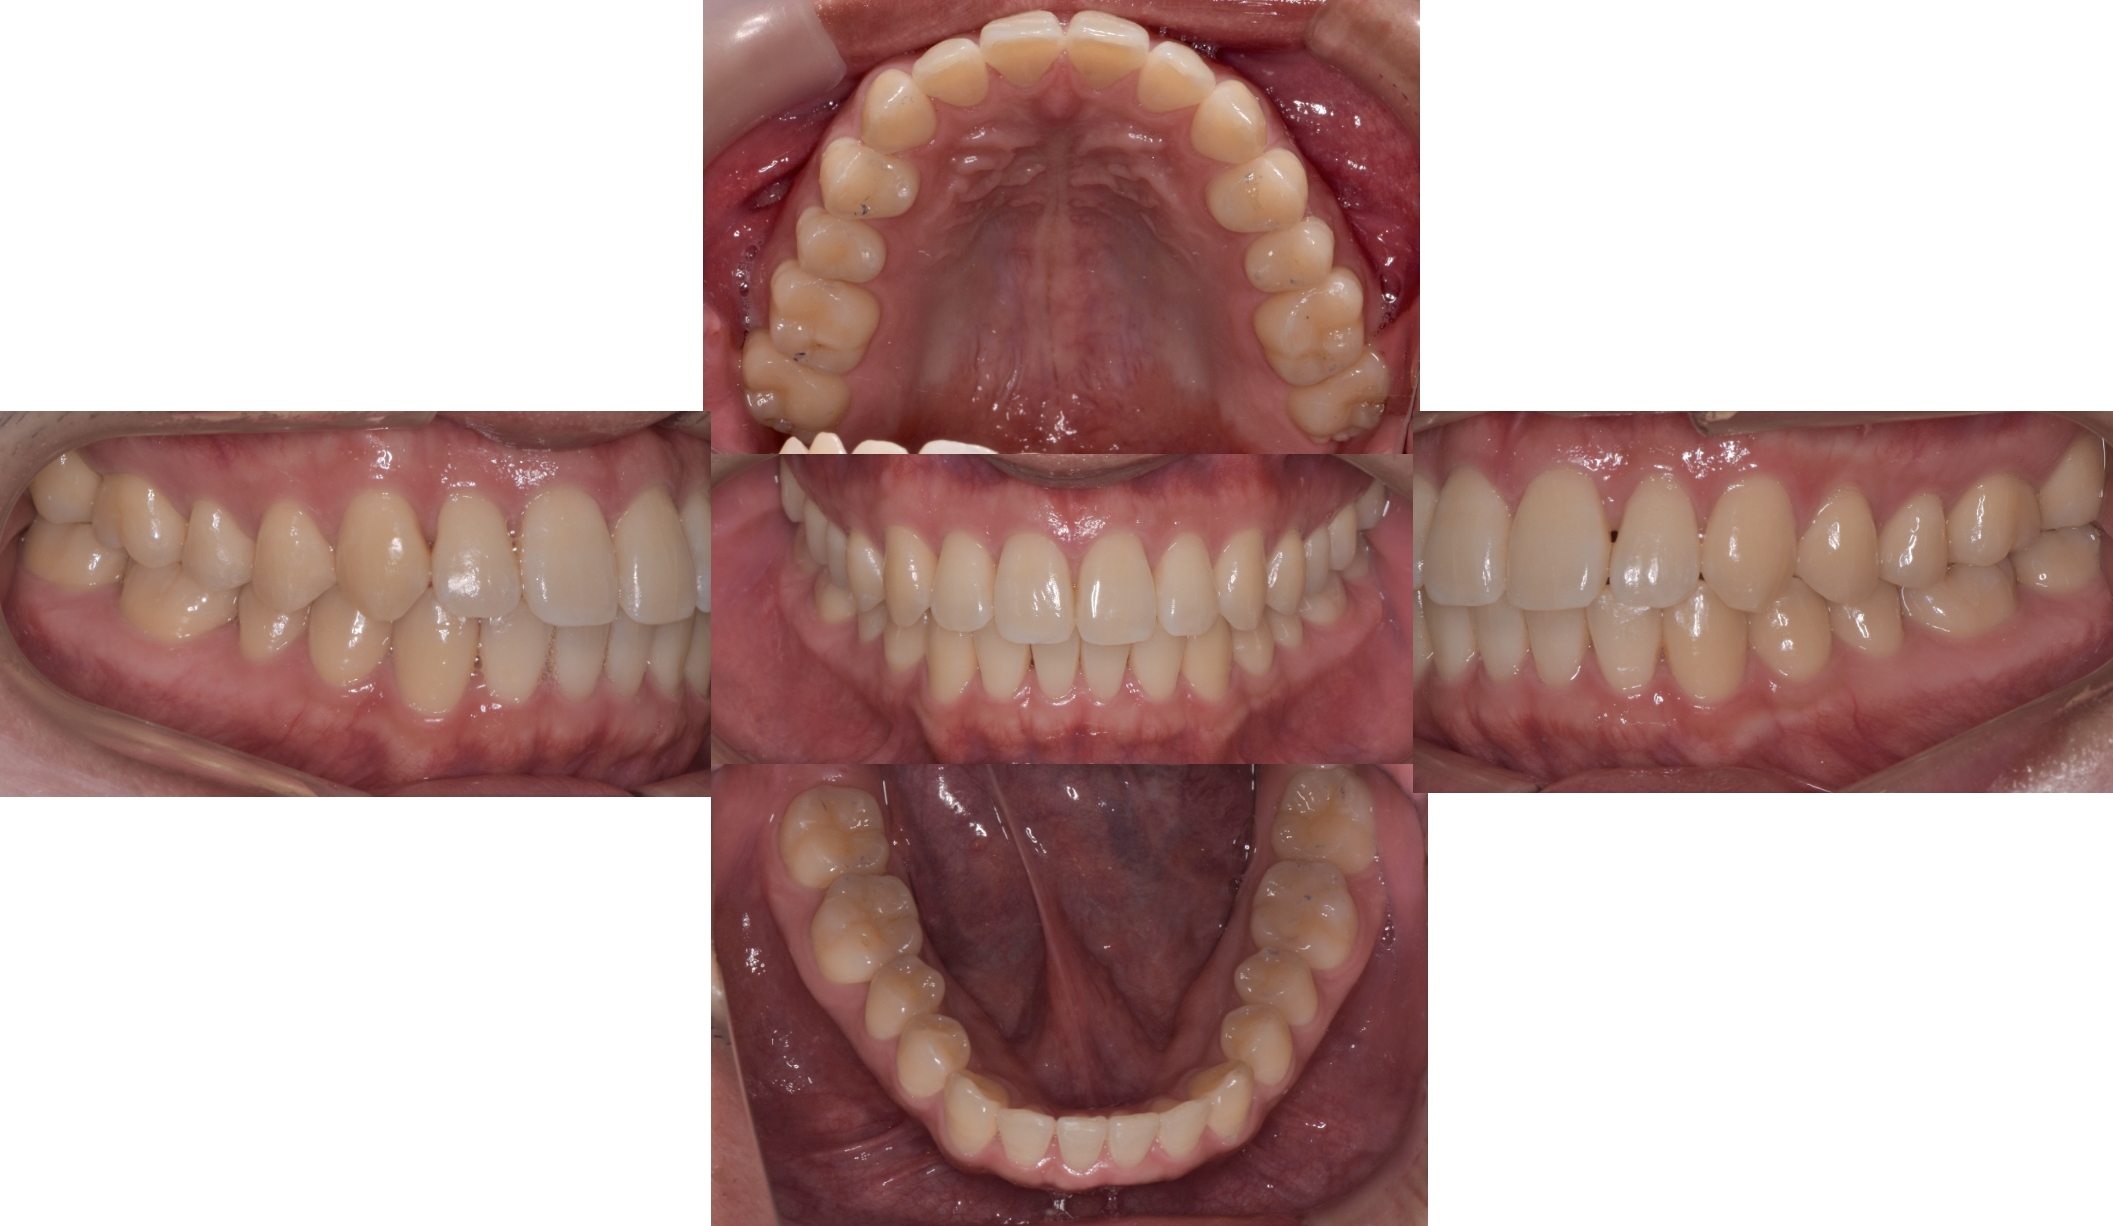

噛めないということを主訴にご来院されました。ただパッと見るとどこが噛んでいないのだろうと言うくらい綺麗な歯をされています。デンタルドックによる精密検査の結果、動画で解説しているように、口腔内写真をみると歯に隙間があったり、所々咬んでいないところも確認できます。ただし口腔内写真だけでは、どの歯がどのように、どんな強さで当たっているのかがわかりません。

前医によって間違った歯並びに矯正されてしまっていたため、マウスピース型矯正(インビザライン)で適正な位置に歯を動かす再治療をおこないました。ただし再矯正後に、T-scan でデータ計測をしたところ、奥歯にまだ強い力が加わっていることが確認出来ます。

このように矯正治療だけで歯並びと噛み合わせが改善することは稀で、ネット広告やホームページに溢れている矯正治療で噛み合わせが治ったというのが、幾つかの間違いや嘘を含んでいることがお分かり頂けると思います。

DTR (噛み合わせ)治療

再矯正を経て以前より歯が適正位置となったこのタイミングで T-scan を使ったDTR (噛み合わせ)治療を行いました。これは数マイクロ(ミリではありません)単位で歯を擦り合わせながら T-scan で検証し、これを繰り返していく噛み合わせ治療です。一般的には咬合調整を呼ばれるものですが、赤と青のリボン紙でカチカチと印をつける方法でなくご覧のようにデジタルで力を計測しながら咬合調整をおこなうのが、DTR (噛み合わせ)治療の大きな違いです。

このように DTR治療後の T-scan データをみると治療前に比較し全体が均等に咬み合っているのがお分かり頂けると思います。

患者さんは今回のマウスピース型矯正(インビザライン)による再矯正、DTR (噛み合わせ)治療を受けた3ヶ月後には、データ上だけではなく快適に咬め、それが安定していることを実感できたそうです。また従来からお悩みであった耳管開放症の症状が自覚できないほどに改善したとの事でした。あくまで耳管開放症の改善は副次的な変化ですが、このように正しい噛み合わせと顎関節治療は体のさまざまな箇所に影響します。